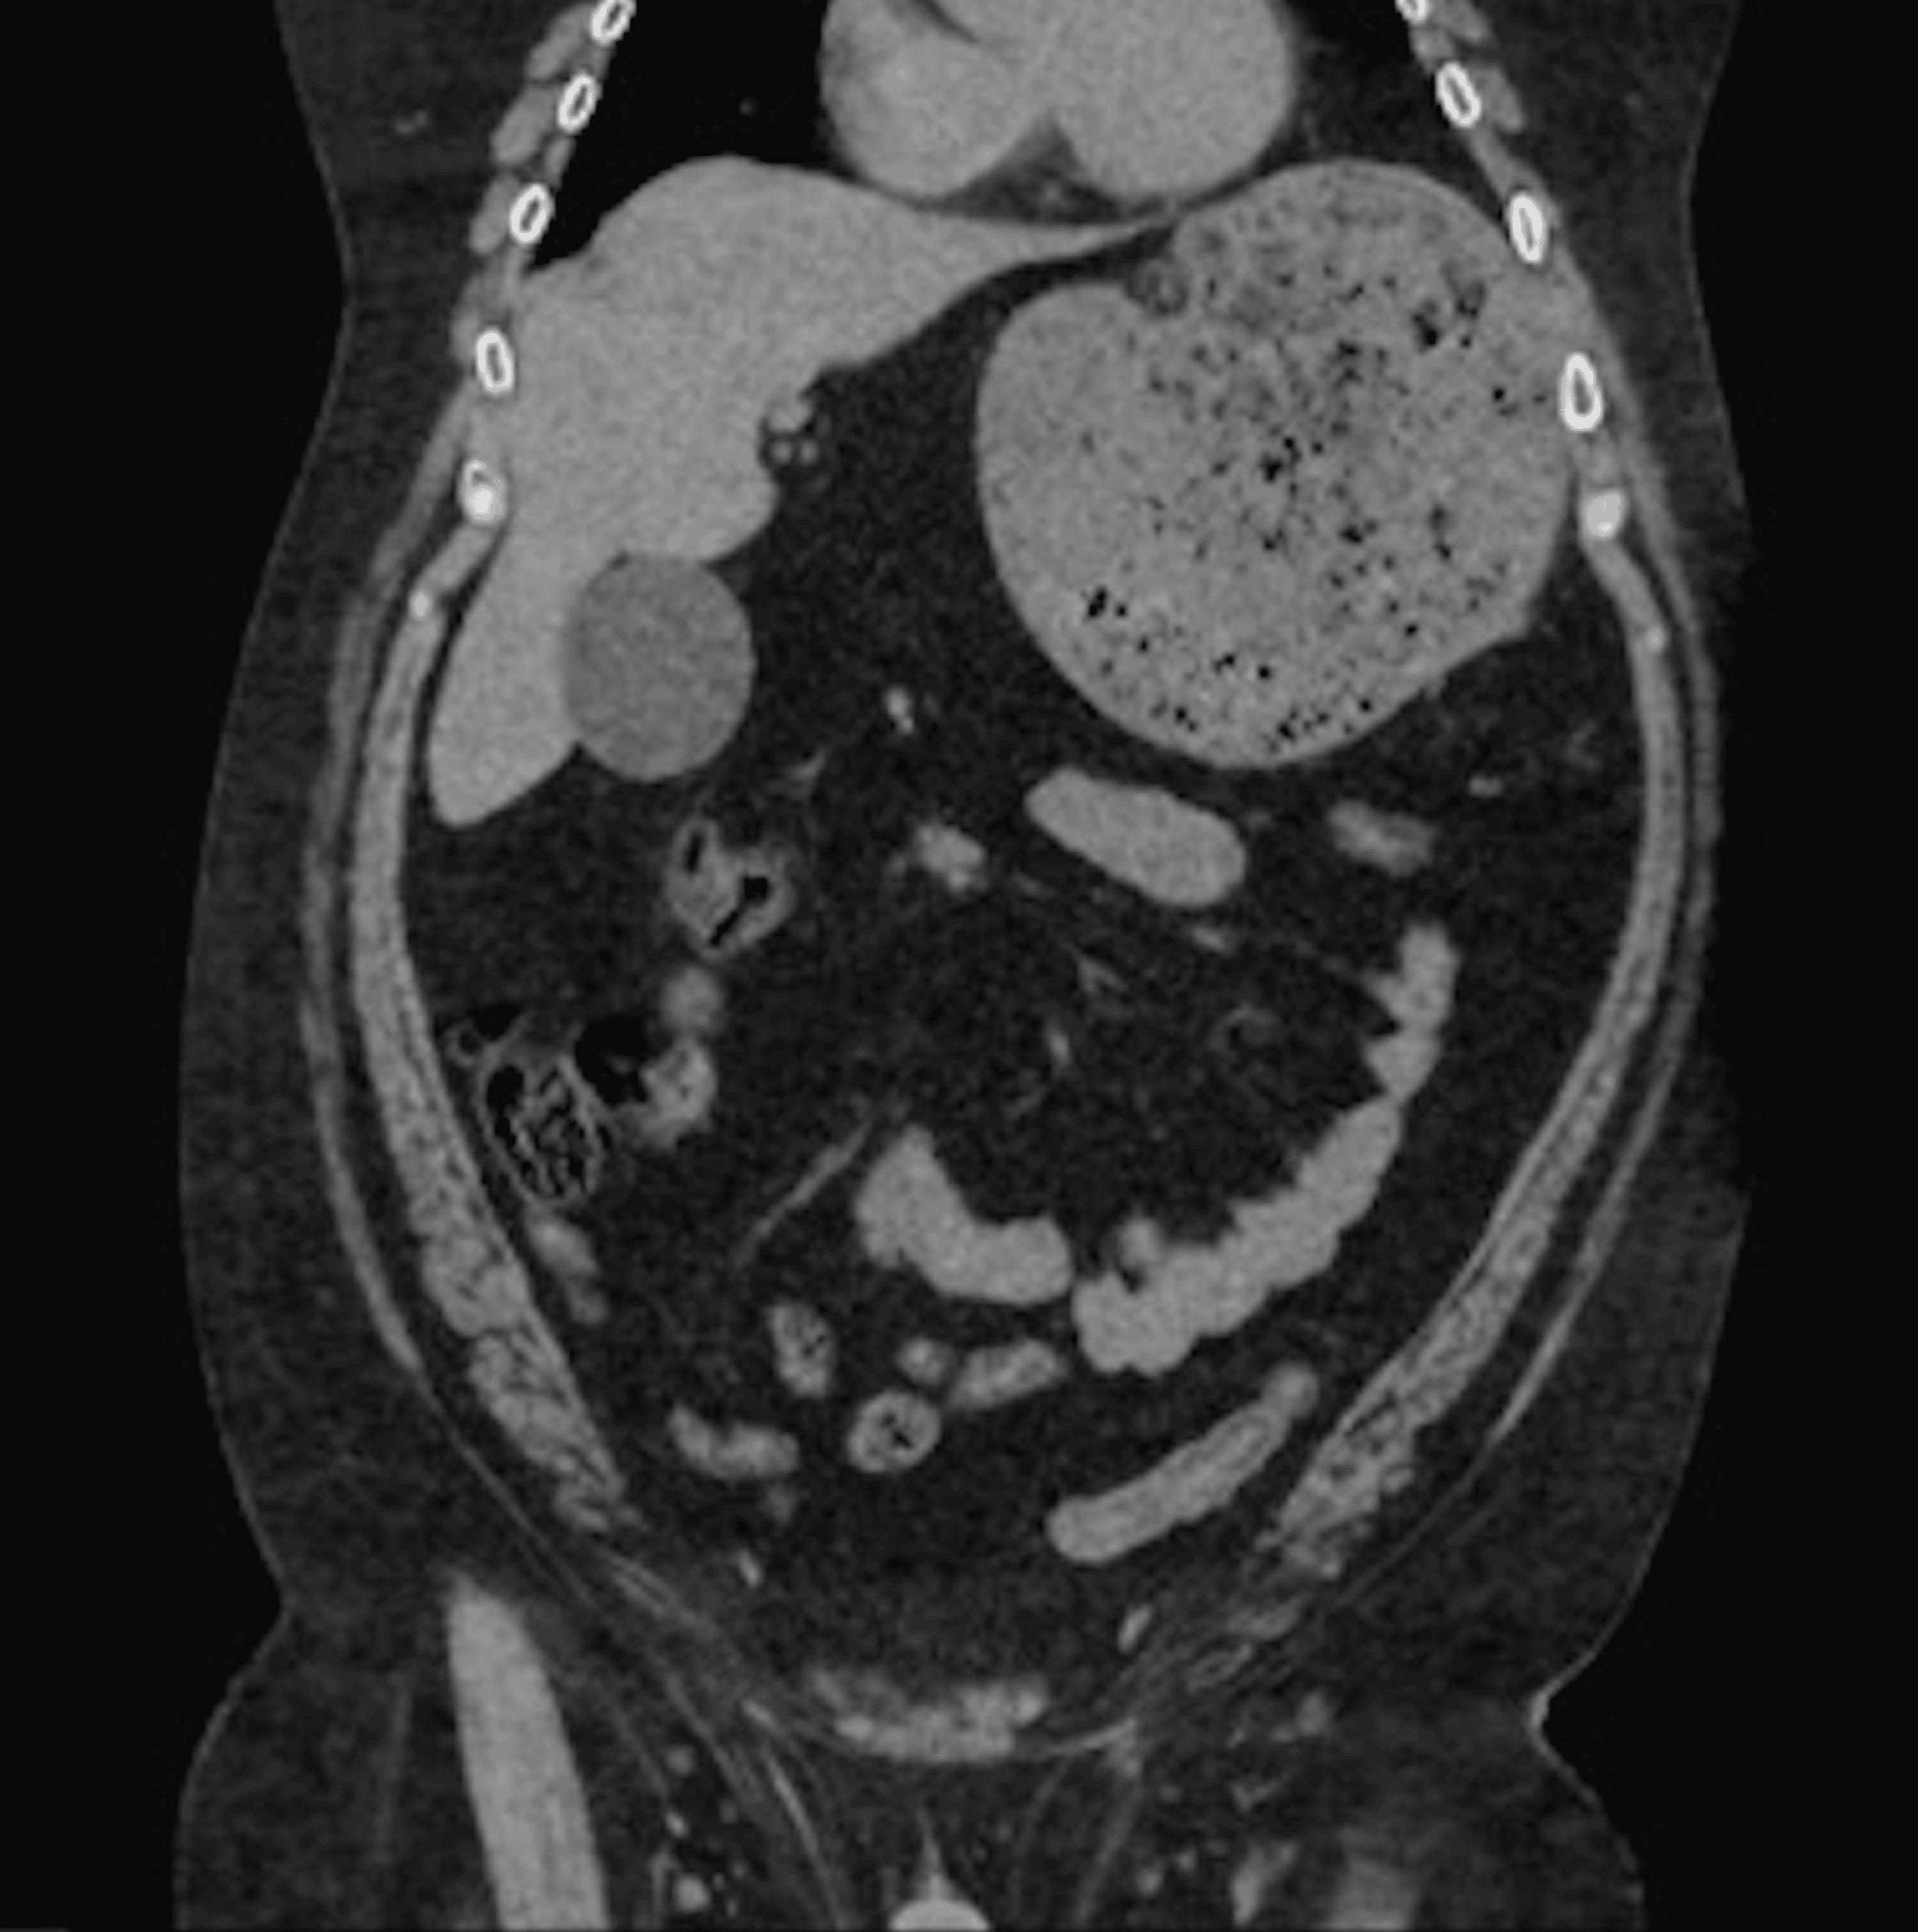

Figure 1 from Endoscopic reduction of a gastric volvulus associated Endoscopic Decompression Gastric Volvulus Although the exact role of endoscopy is still not entirely clear in treating volvulus, endoscopic techniques for volvulus. If there is acute gastric distention due to gastric volvulus, an immediate gastric decompression at the bedside required (with a. Patients who present with acute gastric volvulus without evidence of critical illness (ie gastric necrosis, ischemia, or sepsis) can be managed. Gastric. Endoscopic Decompression Gastric Volvulus.

Secondary gastric volvulus after successful resolution of perisplenic Endoscopic Decompression Gastric Volvulus Although the exact role of endoscopy is still not entirely clear in treating volvulus, endoscopic techniques for volvulus. The diagnosis of volvulus based on radiographs was supported by endoscopy that revealed abnormal gastric anatomy with twisting of the gastric folds and difficulty in. Gastric volvulus is a condition that is not frequently seen in clinical practice and can present with. Endoscopic Decompression Gastric Volvulus.